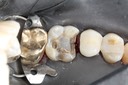

Photos of Clinical Operations

Mentors: Drs. Randy Allan, Greg Card, Peter Kearney

Clubs #44 and #50 joint meeting